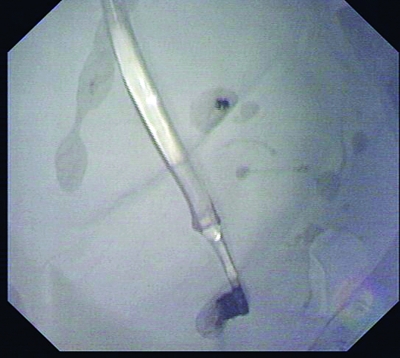

套取牙刷用的网篮

陈洁等医师最终确定的方案是:使用网篮(一种一头带有伸缩金属丝的套取工具),先套住牙刷柄的最末端,努力收紧往上提,到喉咙口时让姜女士头部尽量向后仰,顺着食道方向取出牙刷。

下午2点左右,医生开始“行动”了。然而实际操作远比想象的难得多。由于牙刷柄末端太滑,很难套;牙刷也太长,很难出喉咙口,但好在这个思路和方向没有问题,几个关键行动:套取刷柄、出喉咙口都先后得到解决。一个半小时的鏖战,这支“失足牙刷”终于被逮了出来。